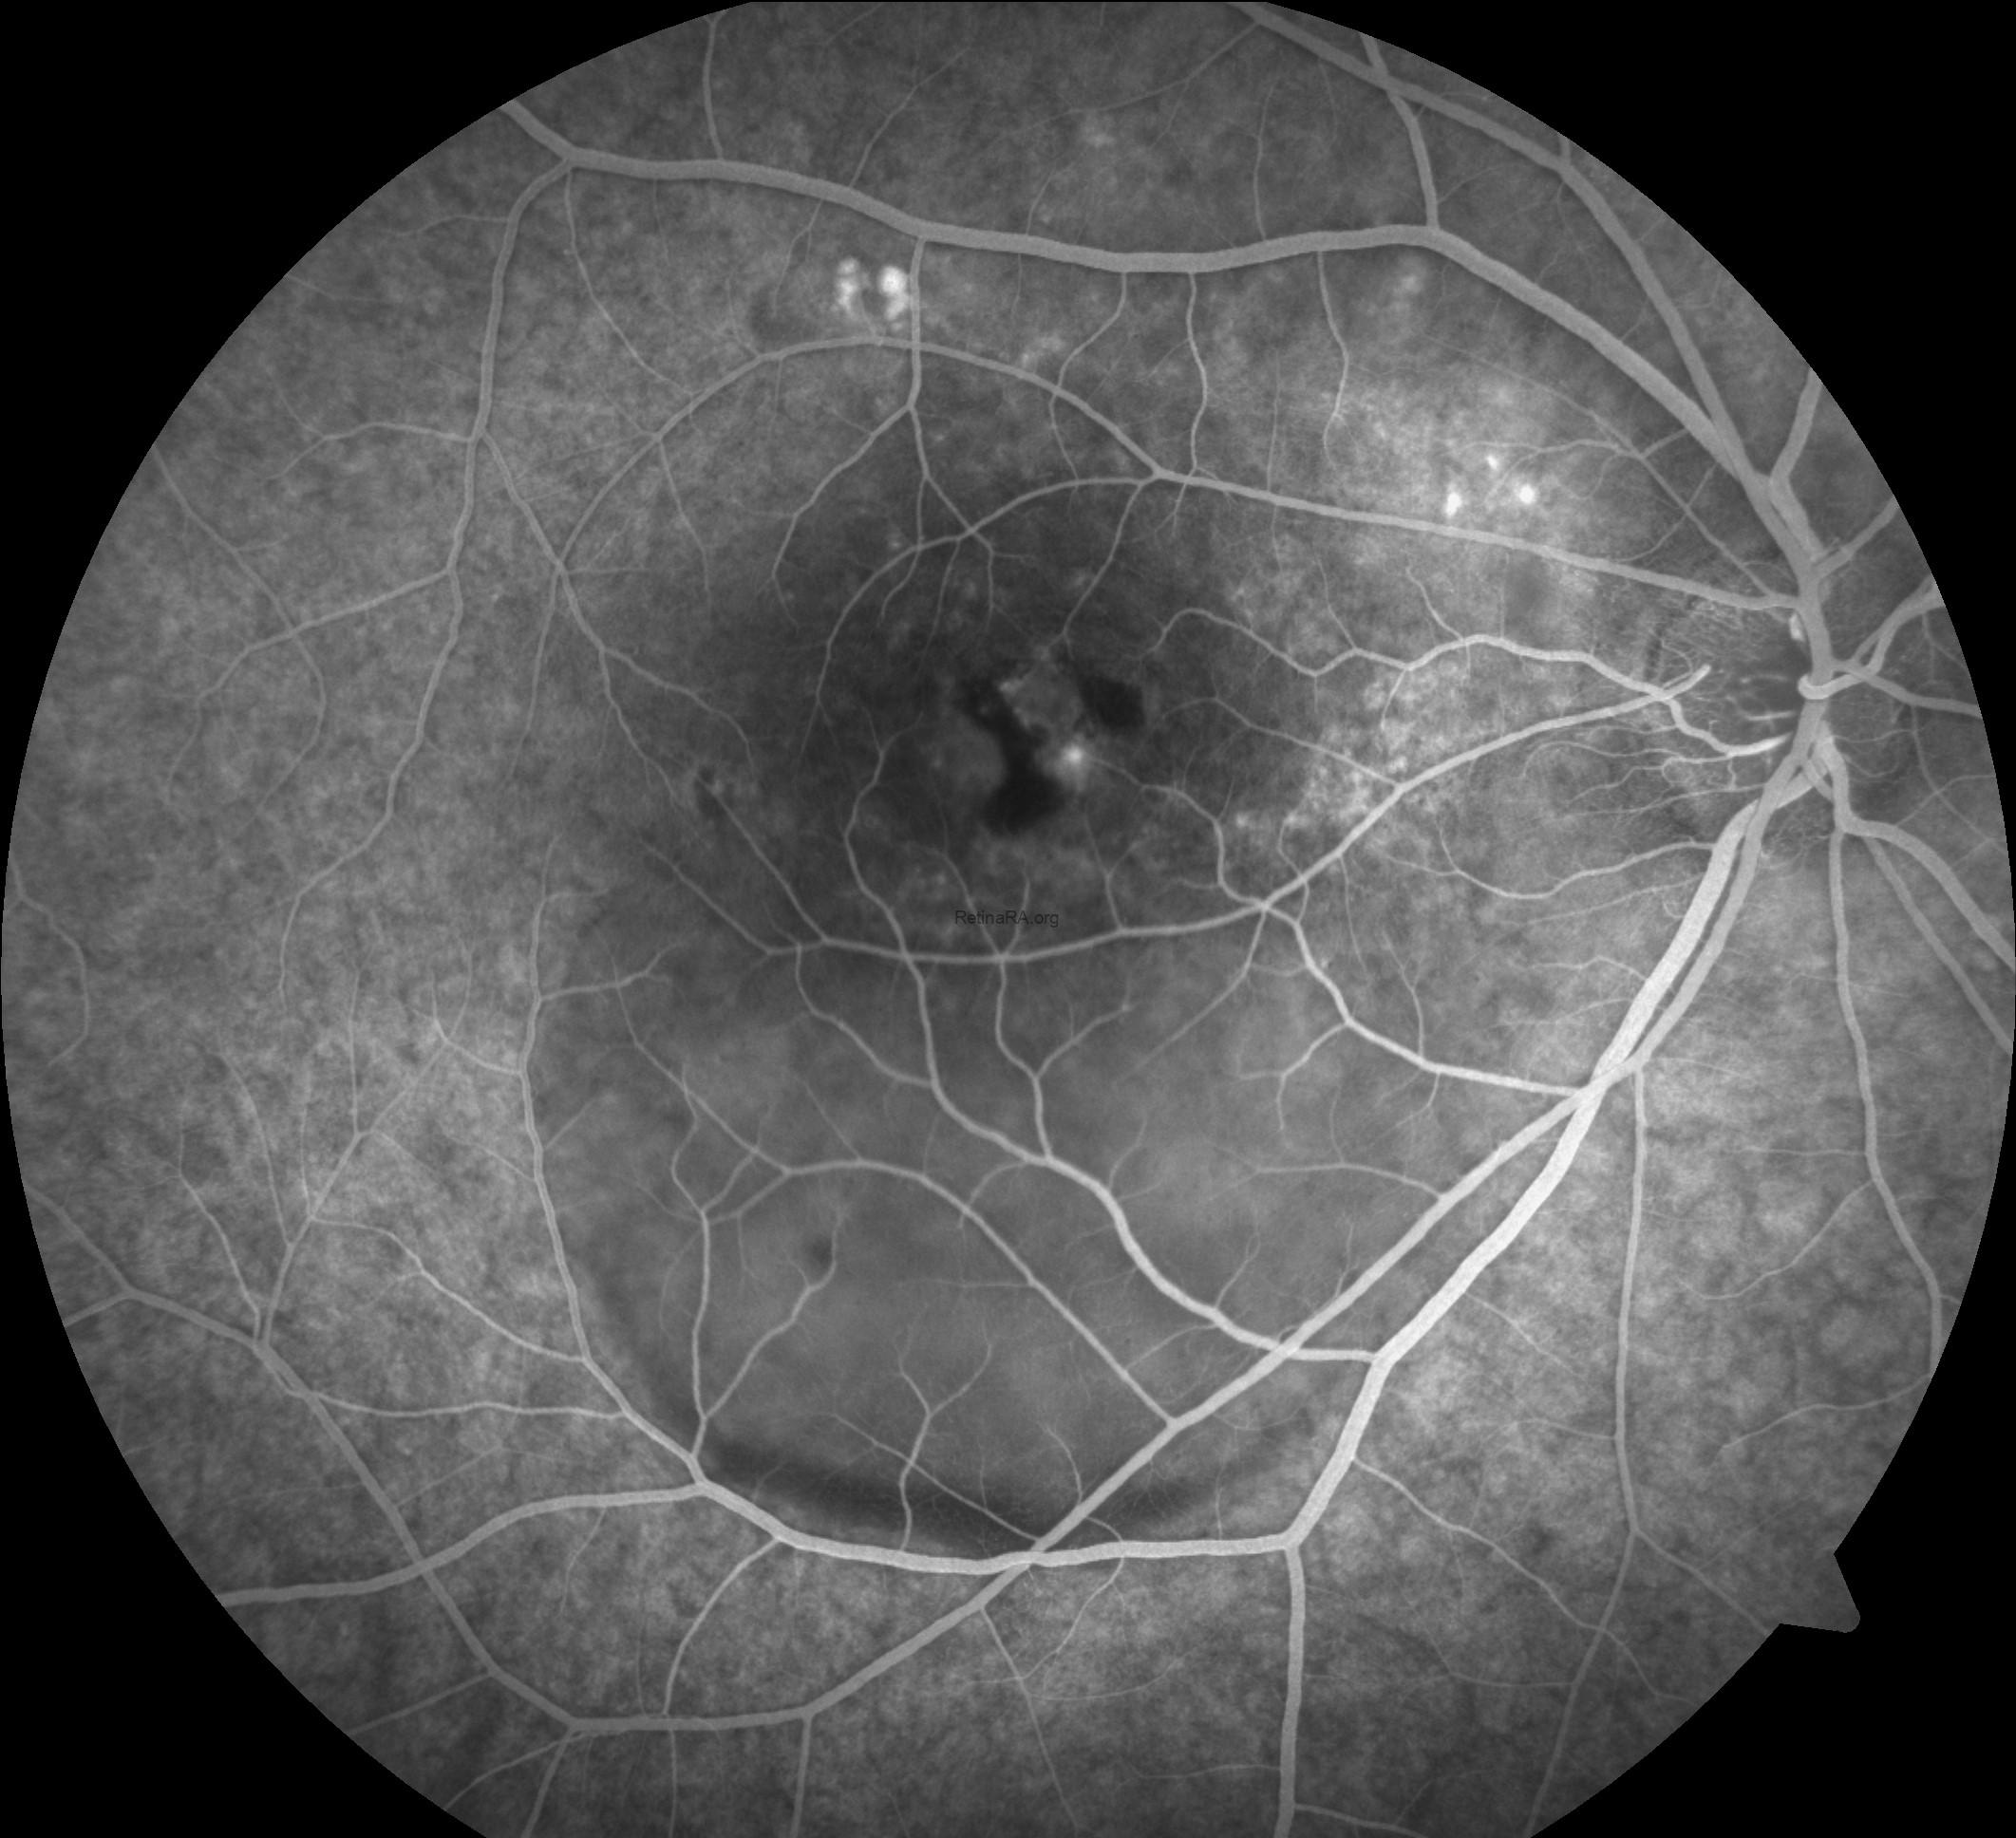

Fluorescein angiography (FFA) of the right eye shows multiple areas of early hyperfluorescence in the macula representing RPE window defects, with a discrete focal leak near the fovea that enlarges over time in an ink-blot pattern. As the study progresses, dye accumulates in the subretinal space with evident pooling and a descending gravitational tract toward the inferior posterior pole, matching the clinically visible detachment. Late frames demonstrate persistent pooling with diffuse staining of chronically altered RPE and the margins of shallow, irregular PEDs, while the optic disc remains non-leaky. There is no lacy capillary network, stippled hyperfluorescence with late leakage, or other features suggestive of choroidal neovascularization, and no vasculitis or peripheral ischemia. Overall, the angiographic pattern is consistent with chronic central serous chorioretinopathy and correlates with OCT-documented subretinal fluid and PED.